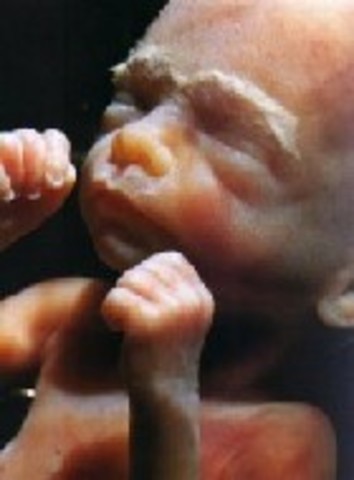

• Week Nine: Fingers and Toes Form

Week Nine: Fingers and Toes Form

The baby's eyelids start to form. Aslo the toes and fingers are starting to develope. Finally the main construction the heart is made.

• Week Ten: Embryo is Now a Fetus

Week Ten: Embryo is Now a Fetus

The embryo is now called a fetus. The muscles are mostly developed.The fingerprint can now be seen.